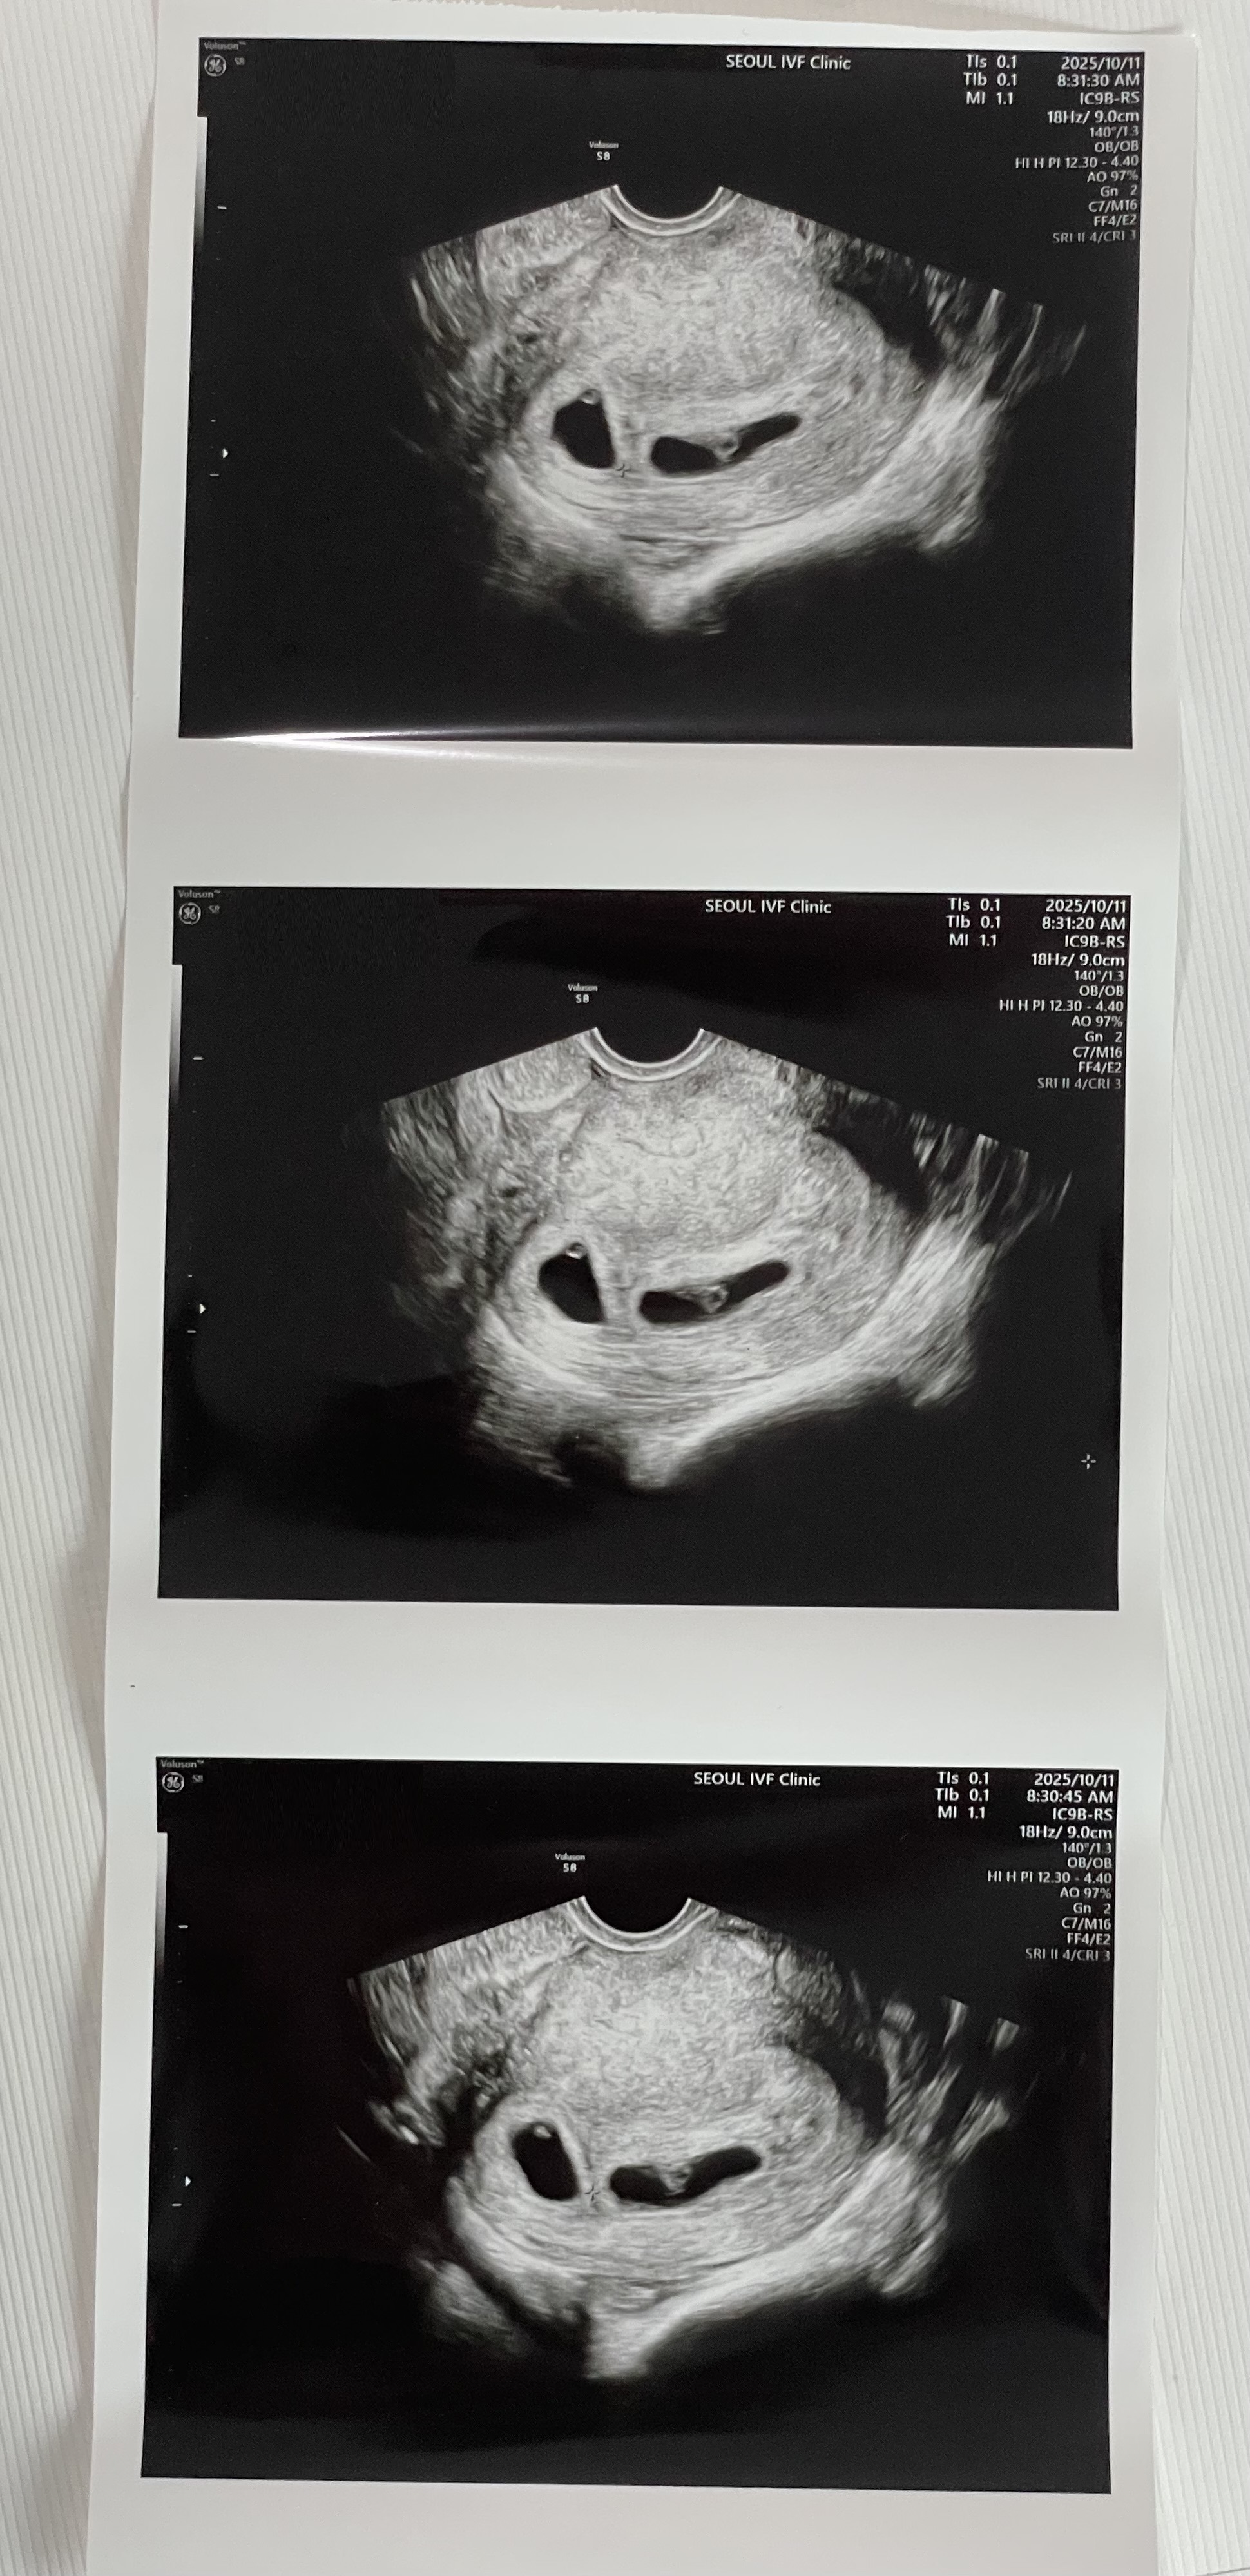

| 가슴 떨리는 임신 이야기를 공유해 주세요. | 인공수정은 성공 확률이 높지 않다는 걸 알고 있었기 때문에 큰 기대는 하지 않았어요. 그런데 한 번에 성공했다는 말을 들었을 때 얼떨떨했고, 나중에 카페 가서 남편에게 전화하면서 정말 많이 울었습니다. 기쁨, 두려움, 벅참이 한꺼번에 밀려와 말로 설명하기 어려운 감정이었어요. |

| 치료 도중 느꼈던 가장 기뻤던 순간과 절망적인 것들은 무엇인가요? 잊지 못할 경험이 있나요? | 가장 기뻤던 순간은 단연 아이가 생겼다는 소식을 들었던 그날이었어요. 절망적인 순간은 크게 없었지만, 시술에 대해 잘 모르는 상태에서 시작해야 했던 초반 걱정 정도였던 것 같아요. |